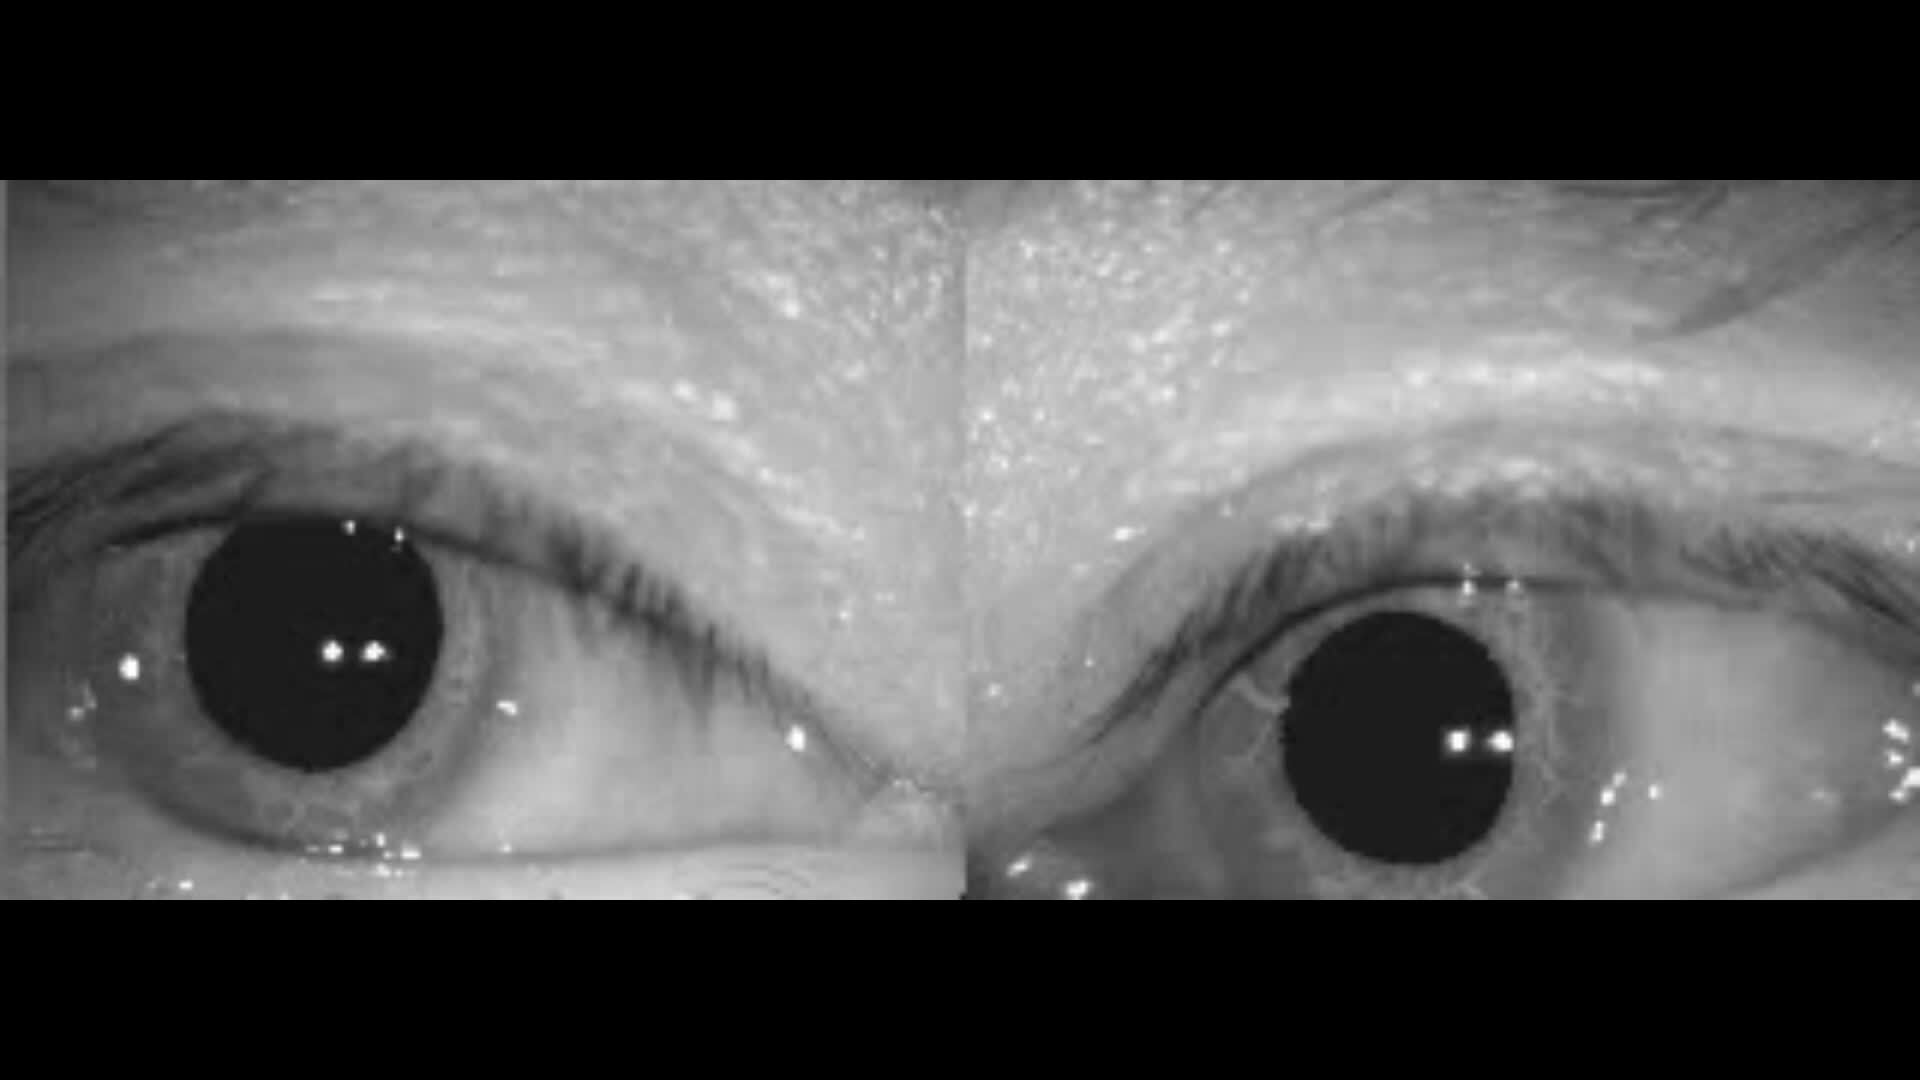

水平半规管的管石症最常见,患者表现为躺在床上左右翻身时出现头晕眩晕,患者的眼震表现为水平为主,略带旋转。视频所示是一例右侧水平半规管管石症的患者,视频1是患者躺在床上右侧翻身时出现水平向右的眼震,专业说法是向地性眼震。视频2是患者躺着左侧翻身时的眼震,方向向左,但是眼震没有右侧翻身时剧烈。